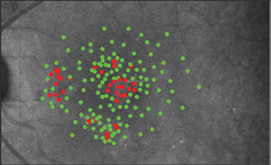

Figures 6a (left) and b (right) show SLO macular perimetry of OS. In Figure 6a, fixation is at the cross. Red dots indicate stimuli not appreciated by patient (50000 trolands). Green dots are stimuli appreciated by patient. Figure 6b shows a graphical representation of the functional field loss, used in our research setting. The location of the fovea (F) is estimated using the optic disk and a blurring function that increases with eccentricity diminishes the effect of more peripheral field losses. In this image, blue is scotoma and red is seeing retina.